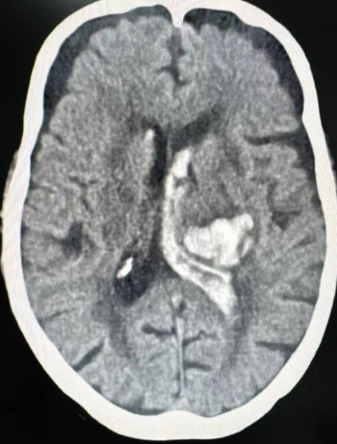

83岁的白奶奶突发意识不清状况,情况危急,随即由120紧急送至陕西冶金医院急诊医学科。头颅CT扫描显示:左侧丘脑、基底节区及侧脑室旁出现急性脑出血,且已破入脑室系统,情况危急。

脑出血作为脑部疾病中较为常见的危急重症,具有发病凶险、病情变化迅速以及致残致死率高的特点。鉴于此,急诊医学科医生迅速联系神经外科主任许春旺进行会诊。在与家属充分沟通病情后,当即为老人开通绿色通道。

在完善相关术前检查并获得家属同意后,老人从急诊医学科被送入手术室,神经外科团队立即对患者实施“脑室穿刺引流术”。经过一小时的紧张手术,手术顺利完成,患者转危为安。为老人的康复之路迈出了关键的第一步。